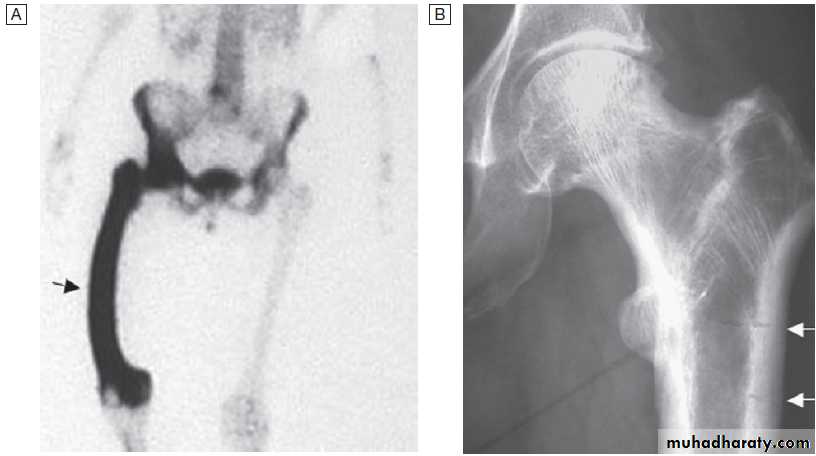

rheumatic diseasesRadionuclide bone scan

This is useful in patients suspected of having metastatic bone disease and Paget’s disease. It involves gamma-camera imaging following an intravenous injection of 99mTc-bisphosphonate. Early post-injection images reflect vascularity and can show increased perfusion of inflamed synovium, Pagetic bone, or primary or secondary bone tumours. Delayed images taken a few hours later reflect bone remodelling as the bisphosphonate localises to sites of active bone turnover. Scintigraphy has a high sensitivity for detecting important bone and joint pathology that is not apparent on plain X-rays . Single photon emission computed tomography (SPECT) combines radionuclide imaging with computed tomography. It can provide accurate anatomical localization of abnormal tracer uptake within the bone and is of particular value in the assessment of patients with chronic low back pain of unknown cause.Conditions detected by isotope bone scanning

X-ray of hip showing changes of osteoarthritis. Note

the superior joint space narrowing (N), subchondral sclerosis (S), marginalosteophytes (white arrows) and cysts (C).